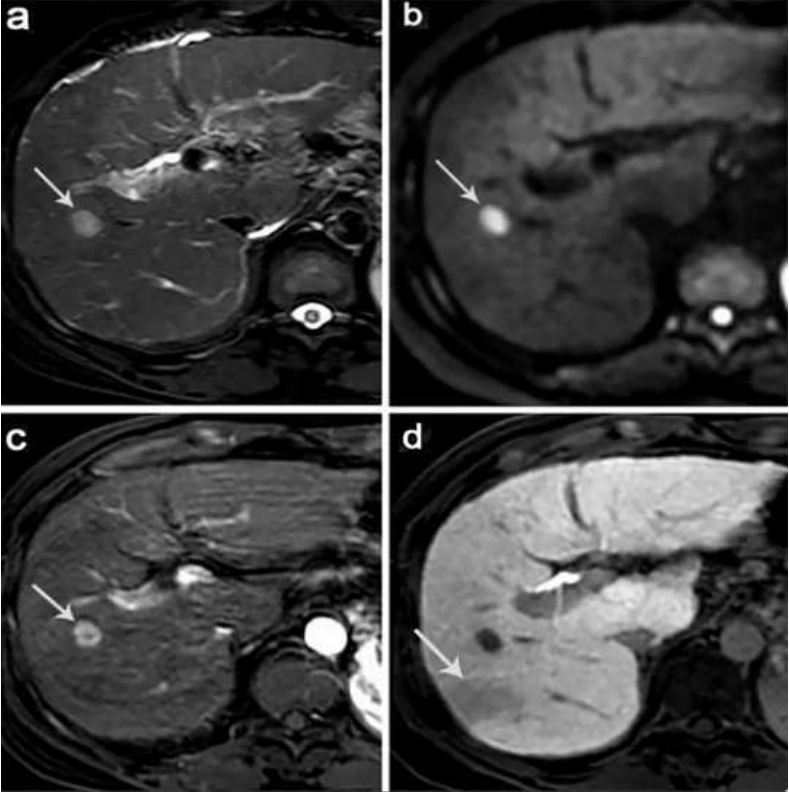

(a) The tumor was approximately 4.9 cm in diameter with unevenly high signals on T2 WI. (b) The mass (arrow) shows diffusion restriction with high SI on a diffusion-weighted image (b = 800 sec/mm2). (c) Gadoxetic acid–enhanced arterial phase MR image shows a hypervascular mass with peritumoral enhancement (arrow). (d) In the hepatobiliary phase (HBP), the mass showed peritumoral hypointensity (arrowheads). On histopathology after hepatectomy, the tumor was classified as Edmondson-Steiner grade III HCC without microvascular invasion.